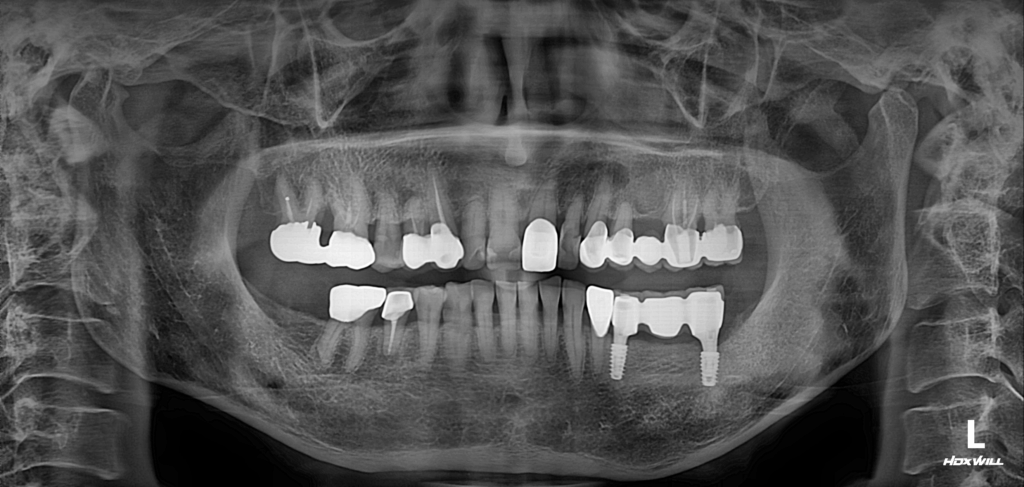

술전 사진

2023.10.19

환자분은 왼쪽 아래 브릿지 부분에 문제가 발생하여 내원하셨습니다.

현재 왼쪽 아래에 위치한 소구치와 대구치가 주로 저작 기능을 담당해왔습니다. 이렇게 한 두 개의 치아에 모든 저작력을 의존하게 되면, 아무리 관리가 잘 되어도 일반적인 자연치아보다 수명이 짧을 수밖에 없습니다.

소구치는 큰 문제가 없었으나, 후방의 대구치 부위는 주변 골 소실이 심해지고, 치아 동요도 확인되었습니다. 따라서 소구치는 유지하고, 후방에 위치한 보철물과 대구치는 발치한 뒤, 브릿지 임플란트를 식립하기로 했습니다.